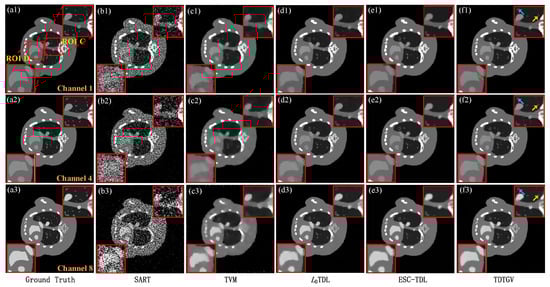

Figure 12 and Figure 13 show the images reconstructed using SART, TVM, L0TDL, ESC-TDL, and the proposed algorithm TDTGV at 120 and 60 views, respectively. From the figures, it could be seen that the SART algorithm reconstructs images with severe noise and artifacts, resulting in the loss of image details. The TVM algorithm exhibits image blurring in soft tissue regions, as shown in Figure 12(b1–b3) and Figure 13(b1–b3). The L0TDL and ESC-TDL algorithms improve the edge protection of images to some extent, but they also suffer from the loss of some fine image structures, as illustrated in Figure 12(c1–c3,d1–d3) and Figure 13(c1–c3,d1–d3). In comparison to the previous algorithms, the proposed TDTGV algorithm performs best in terms of reconstructed image quality, as shown in Figure 12(e1–e3) and Figure 13(e1–e3), recovering more fine structures. At the same time, it can be observed from the enlarged views of regions B and D in the figures that the TDTGV algorithm can effectively suppress artifacts that appear near bones, as indicated by arrows “1”, “2”, “3”, and “4”.

In order to further verify the effectiveness of the algorithm proposed in this paper, regions of interest A and C were extracted from Figure 12 and Figure 13 and enlarged for separate display in Figure 14. From the enlarged images of the regions of interest, it can be observed that the image quality obtained by reconstructing with SART and TVM algorithms is relatively low, making it difficult to distinguish the image structures indicated by the red arrows. For the image structure indicated by red arrow “6”, the reconstruction using the L0TDL algorithm appears blurred, while the ESC-TDL algorithm and the TDTGV algorithm yield clearer image structures. However, the ESC-TDL algorithm also exhibits some blurriness for the image structure shown by red arrow “5”. For the bone structure indicated by arrow “7”, all compared algorithms exhibit varying degrees of blurriness. In comparison, the TDTGV algorithm yields a clearer structure, further verifying the effectiveness of the proposed algorithm.

Figure 13. Images representing actual clinical mice reconstructed from 60 projections using different methods: (a1a3) SART, (b1b3) TVM, (c1c3) L0TDL, (d1d3) ESC-TDL, and (e1e3) TDTGV. The display windows are [0, 0.08] cm−1.